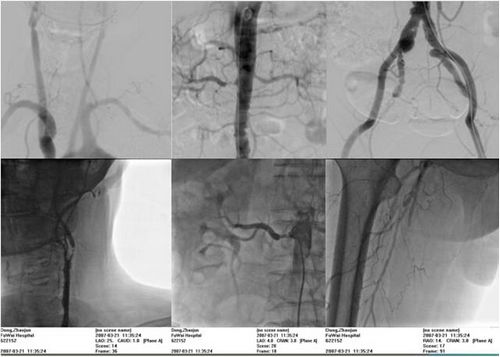

首先给大家举一个例子:患者,74岁,男性,劳力性胸痛,间歇性跛行,高血压伴反复头晕。从冠状动脉造影中可以看到冠状动脉左主干、冠状动脉前降支、冠状动脉回旋支、还有右冠状动脉都严重的狭窄,甚至都有闭塞。

就疾病目前的状况来讲,大夫一般会建议做搭桥,但是做搭桥之前,我们做了进一步的血管造影诊断,发现右侧的肾动脉严重的狭窄,左侧的颈内动脉严重狭窄,右侧的股浅动脉闭塞。所以影像学特点提示是严重冠心病,多支病变的患者要注意合并全身的周围血管动脉狭窄的问题。